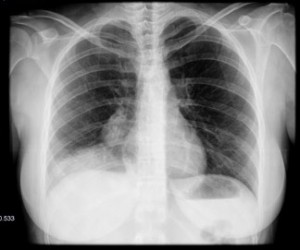

La radiografía simple de tórax debe ser siempre el estudio inicial en todos los pacientes con sospecha de patología torácica, debido a la gran cantidad de información que nos proporciona para el diagnóstico de enfermedades respiratorias, y especialmente por tratarse de una prueba radiológica fácil, barata, rápida, reproducible y que utiliza poca radiación.

Haz click en las imágenes para verlas ampliadas